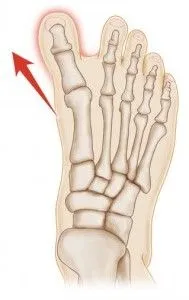

Hallux Varus is a rare complication after Bunion correction surgery to which the big toe was overcorrected.

The following radiograph depicst deviation of the great to away from the lesser toes created enlarged spacing between the great toe and second toe. This makes walking and use of shoegear difficult.